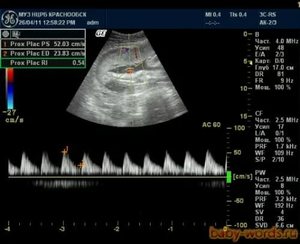

Диагностика

Наиболее эффективным и информативным способом исследования при нарушениях кровообращения является доплерография. Этот метод позволяет обнаружить даже незначительные изменения в кровотоке артерий и вен, а также изучить гемодинамику плода и получить цветное графическое изображение. Благодаря доплерографии можно оценить прогноз текущей беременности и подобрать соответствующее лечение.

Менее точными методами являются УЗИ и КТ, которые позволяют выявить косвенные признаки гипоксии, такие как патологии плаценты и недостаточный вес плода.